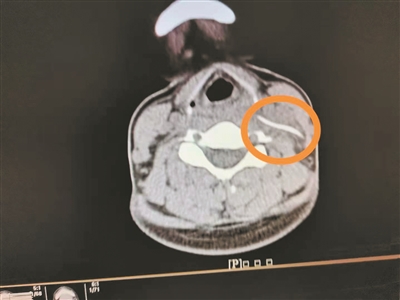

影像檢查顯示頸部異物。

4月1日,陳女士帶女兒到南方醫(yī)科大學(xué)第三附屬醫(yī)院就診,想起自己頸部不舒服,就順便到耳鼻咽喉科就診,副主任醫(yī)師曹慶碩接診后,請患者平躺檢查,此時陳女士感覺頸部更痛了,醫(yī)生懷疑頸部有異物,于是進行了頸部CT平掃,果然發(fā)現(xiàn)左側(cè)頸動脈鞘區(qū)有異物。

明確診斷后,醫(yī)生為陳女士安排4月2日手術(shù),行“頸部側(cè)切開異物取出術(shù)”,術(shù)中見一魚刺橫行于甲狀軟骨平面的咽旁間隙內(nèi),緊貼頸內(nèi)靜脈、頸總動脈后方,周圍炎性組織包裹,幸好頸部血管無損傷,分離包裹的炎性組織,取出異物,長3.3cm。